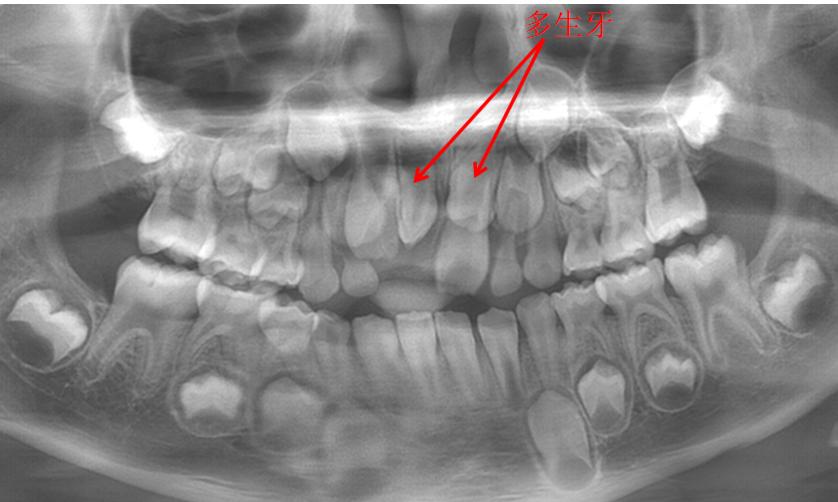

3.恒牙周围有多生牙阻挡

由于多生牙占据了原来要萌出恒牙的位置,导致恒牙移位无法正常萌出。

这种情况就要尽早把多生牙拔除,以免造成更大的影响